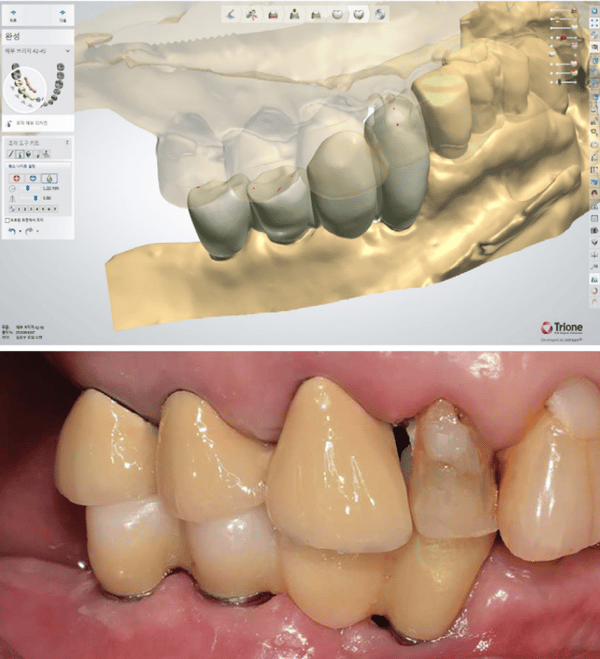

要實現這個大膽的計畫,精準度是唯一的依歸。這裡展現了一個極具價值的臨床技巧:在進行 CT 與口內掃描檔案的疊合時,由於病患口內缺乏足夠的自然牙作為特徵點,且金屬假牙在 CT 上會產生散射干擾,Dr. Lee 巧妙地在牙齦上放置了標記物。這些標記物就像是茫茫大海中的燈塔,讓 Implant Studio 軟體能完美地將骨骼資訊與軟組織資訊鎖定在一起。

手術當天,數位規劃的價值轉化為實質的臨床紅利。由於術前已透過軟體精確計算了植體位置與角度,Dr. Lee 得以執行不翻瓣手術。手術導板與牙齦的密合度極佳,無需額外的骨釘固定,手術過程安靜、快速且出血量極低。這對於病患來說,不再是一場血淋淋的手術,而是一次精密的醫療體驗。

更令人驚艷的是立即受力的環節。利用術前設計好的檔案,醫師在手術當天就為病患裝戴上了臨時贋復物。這裡有一個值得注意的細節:Dr. Lee 並沒有急著製作最終假牙,而是先利用客製化的鈦金屬基台搭配 PMMA 臨時牙冠。

這並非多此一舉,而是為了在軟組織癒合期,透過客製化基台塑形出完美的穿透輪廓,同時利用這段時間重新建立並確認病患的咬合關係。這種「以時間換取空間」的策略,只有在數位流程能夠快速、低成本地製作臨時贋復物的前提下才得以實現。